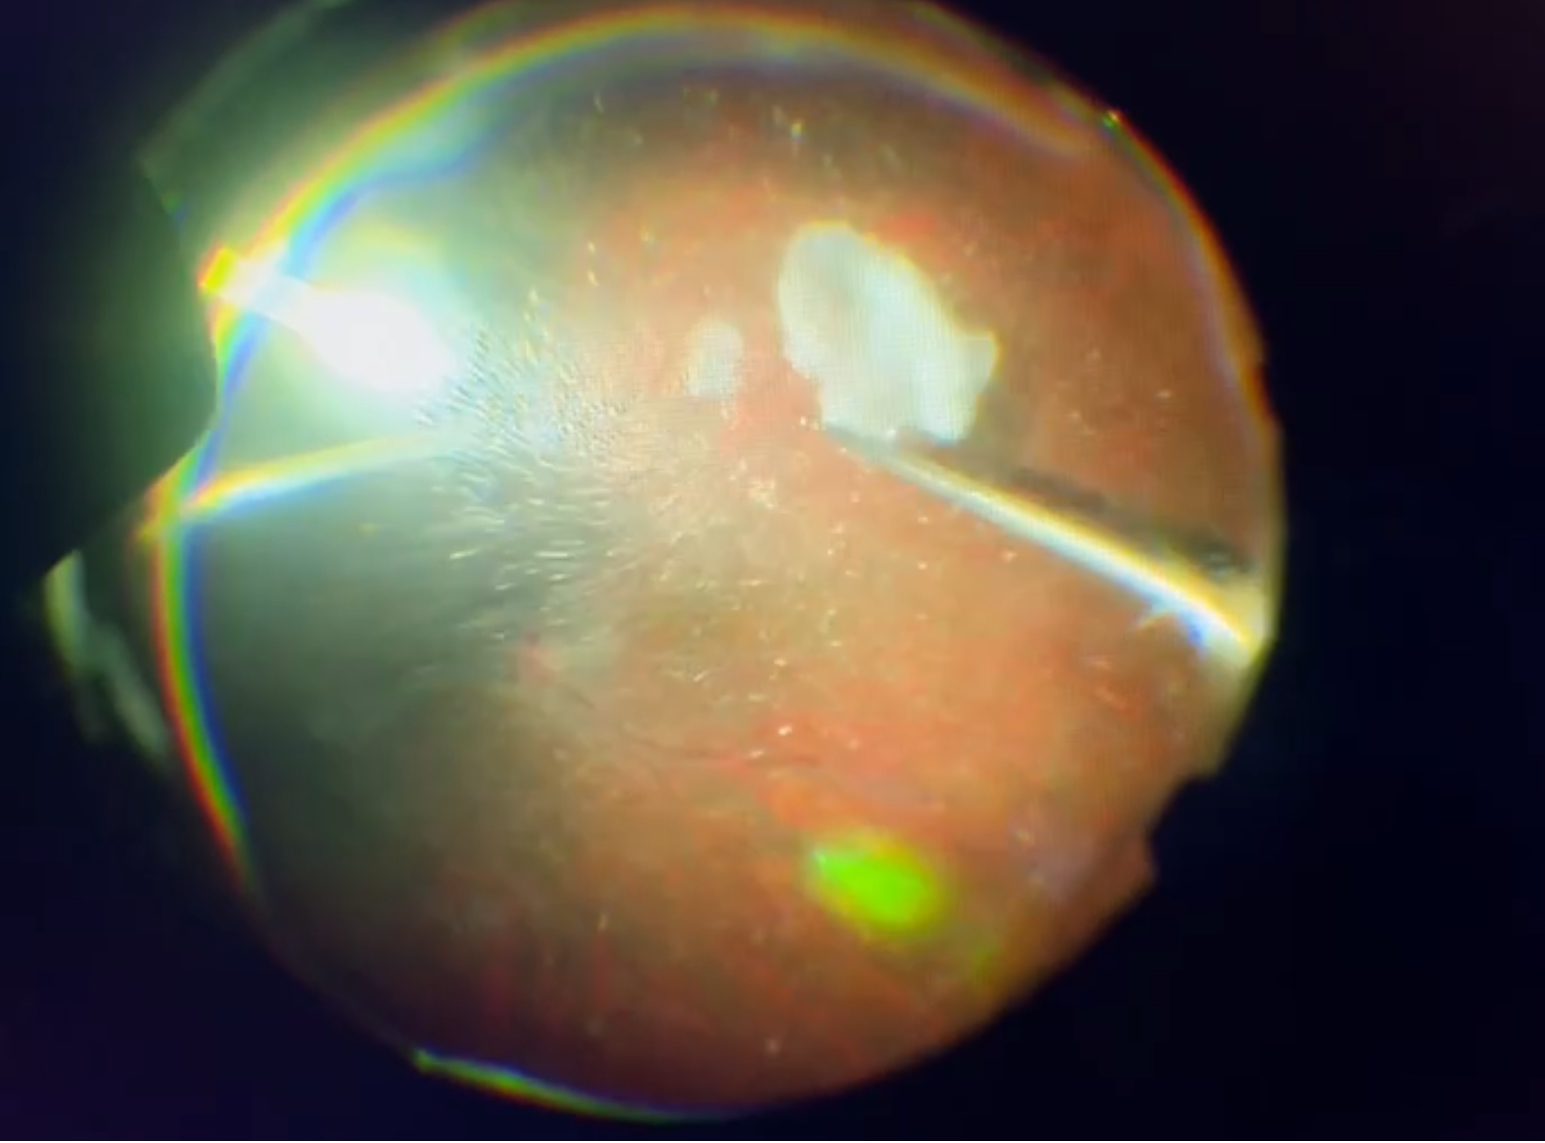

今日の硝子体手術は61歳の女性の方で、先月、白内障の手術をさせていただきましたが、超音波で水晶体の硬い部分(核)を砕いて吸い取る操作の時に、水晶体の袋(水晶体嚢)の後ろ側の部分(後嚢)に裂け目ができてしまう“後嚢破損”を起こしてしまい、水晶体の濁りが眼の奥の方(硝子体の中)に落ちてしまいました(水晶体落下)。小さな濁りはある程度、時間の経過で吸収されていきますが、それまでは飛蚊症として感じますし、この方の場合、大きめの濁りも落ちてしまったので、視野の端の方に大きな影が動いて見えるような症状もあり、また、そのような大きな濁りが長く残ると網膜に炎症を起こす可能性もあったので、今回、その濁りを取るために硝子体手術をさせていただきました。大きな濁りといっても米粒程度で硬さもなく、一瞬で吸い取れてしまいましたが、その他の小さな濁りも結構、多くあったので、硝子体をごときれいに取り、すっきりしてくれるのではと思います。後嚢破損を起こさなければしなくてよい手術でしたし、硝子体の濁りの程度からも飛蚊症の症状はかなりひどかったと思われますが、前回の手術の後も、今回の手術を受ける時も、否定的なことは何もおっしゃらずに、僕の話を聞いて、手術を受けてくださり、本当にありがたいことだと感謝しています。余計な手術を受けていただくことになってしまい、申し訳ありませんでしたが、できる限りの治療を精一杯したつもりですし、これからもしっかり経過を見ていきますので(今回の手術で落ち着いてくれると思いますが!)、どうぞよろしくお願いいたします。